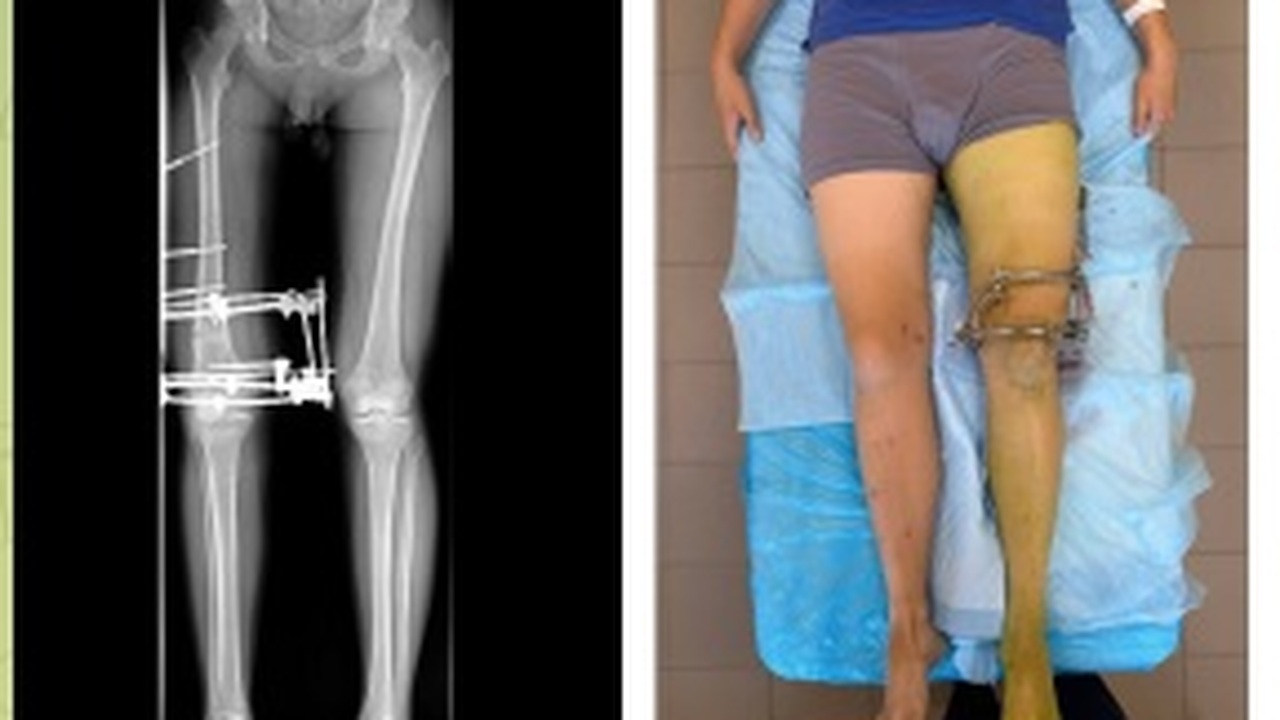

В клиниках Самарского государственного медицинского университета подростку провели успешную коррекцию Х-образной деформации ног. Пациент, начавший заниматься спортом, жаловался на боли в коленях и эстетический дискомфорт.

Хирурги выбрали поэтапный подход: сначала скорректировали ногу с меньшей деформацией, дождались сращения костей и завершения реабилитации, а затем исправили вторую ногу, используя первую как ориентир. Врач-травматолог-ортопед Никита Лихолатов отметил, что это позволило учесть асимметрию и корректно нарастить длину конечности.

Аппарат внешней фиксации сняли в начале декабря, сейчас подросток проходит активную реабилитацию и хорошо себя чувствует. Врачи напоминают, что при отклонениях формы ног у детей важно своевременно наблюдать и при необходимости корректировать деформацию, пока идет рост, чтобы избежать сложных операций и длительного восстановления в будущем, сообщает СамГМУ.